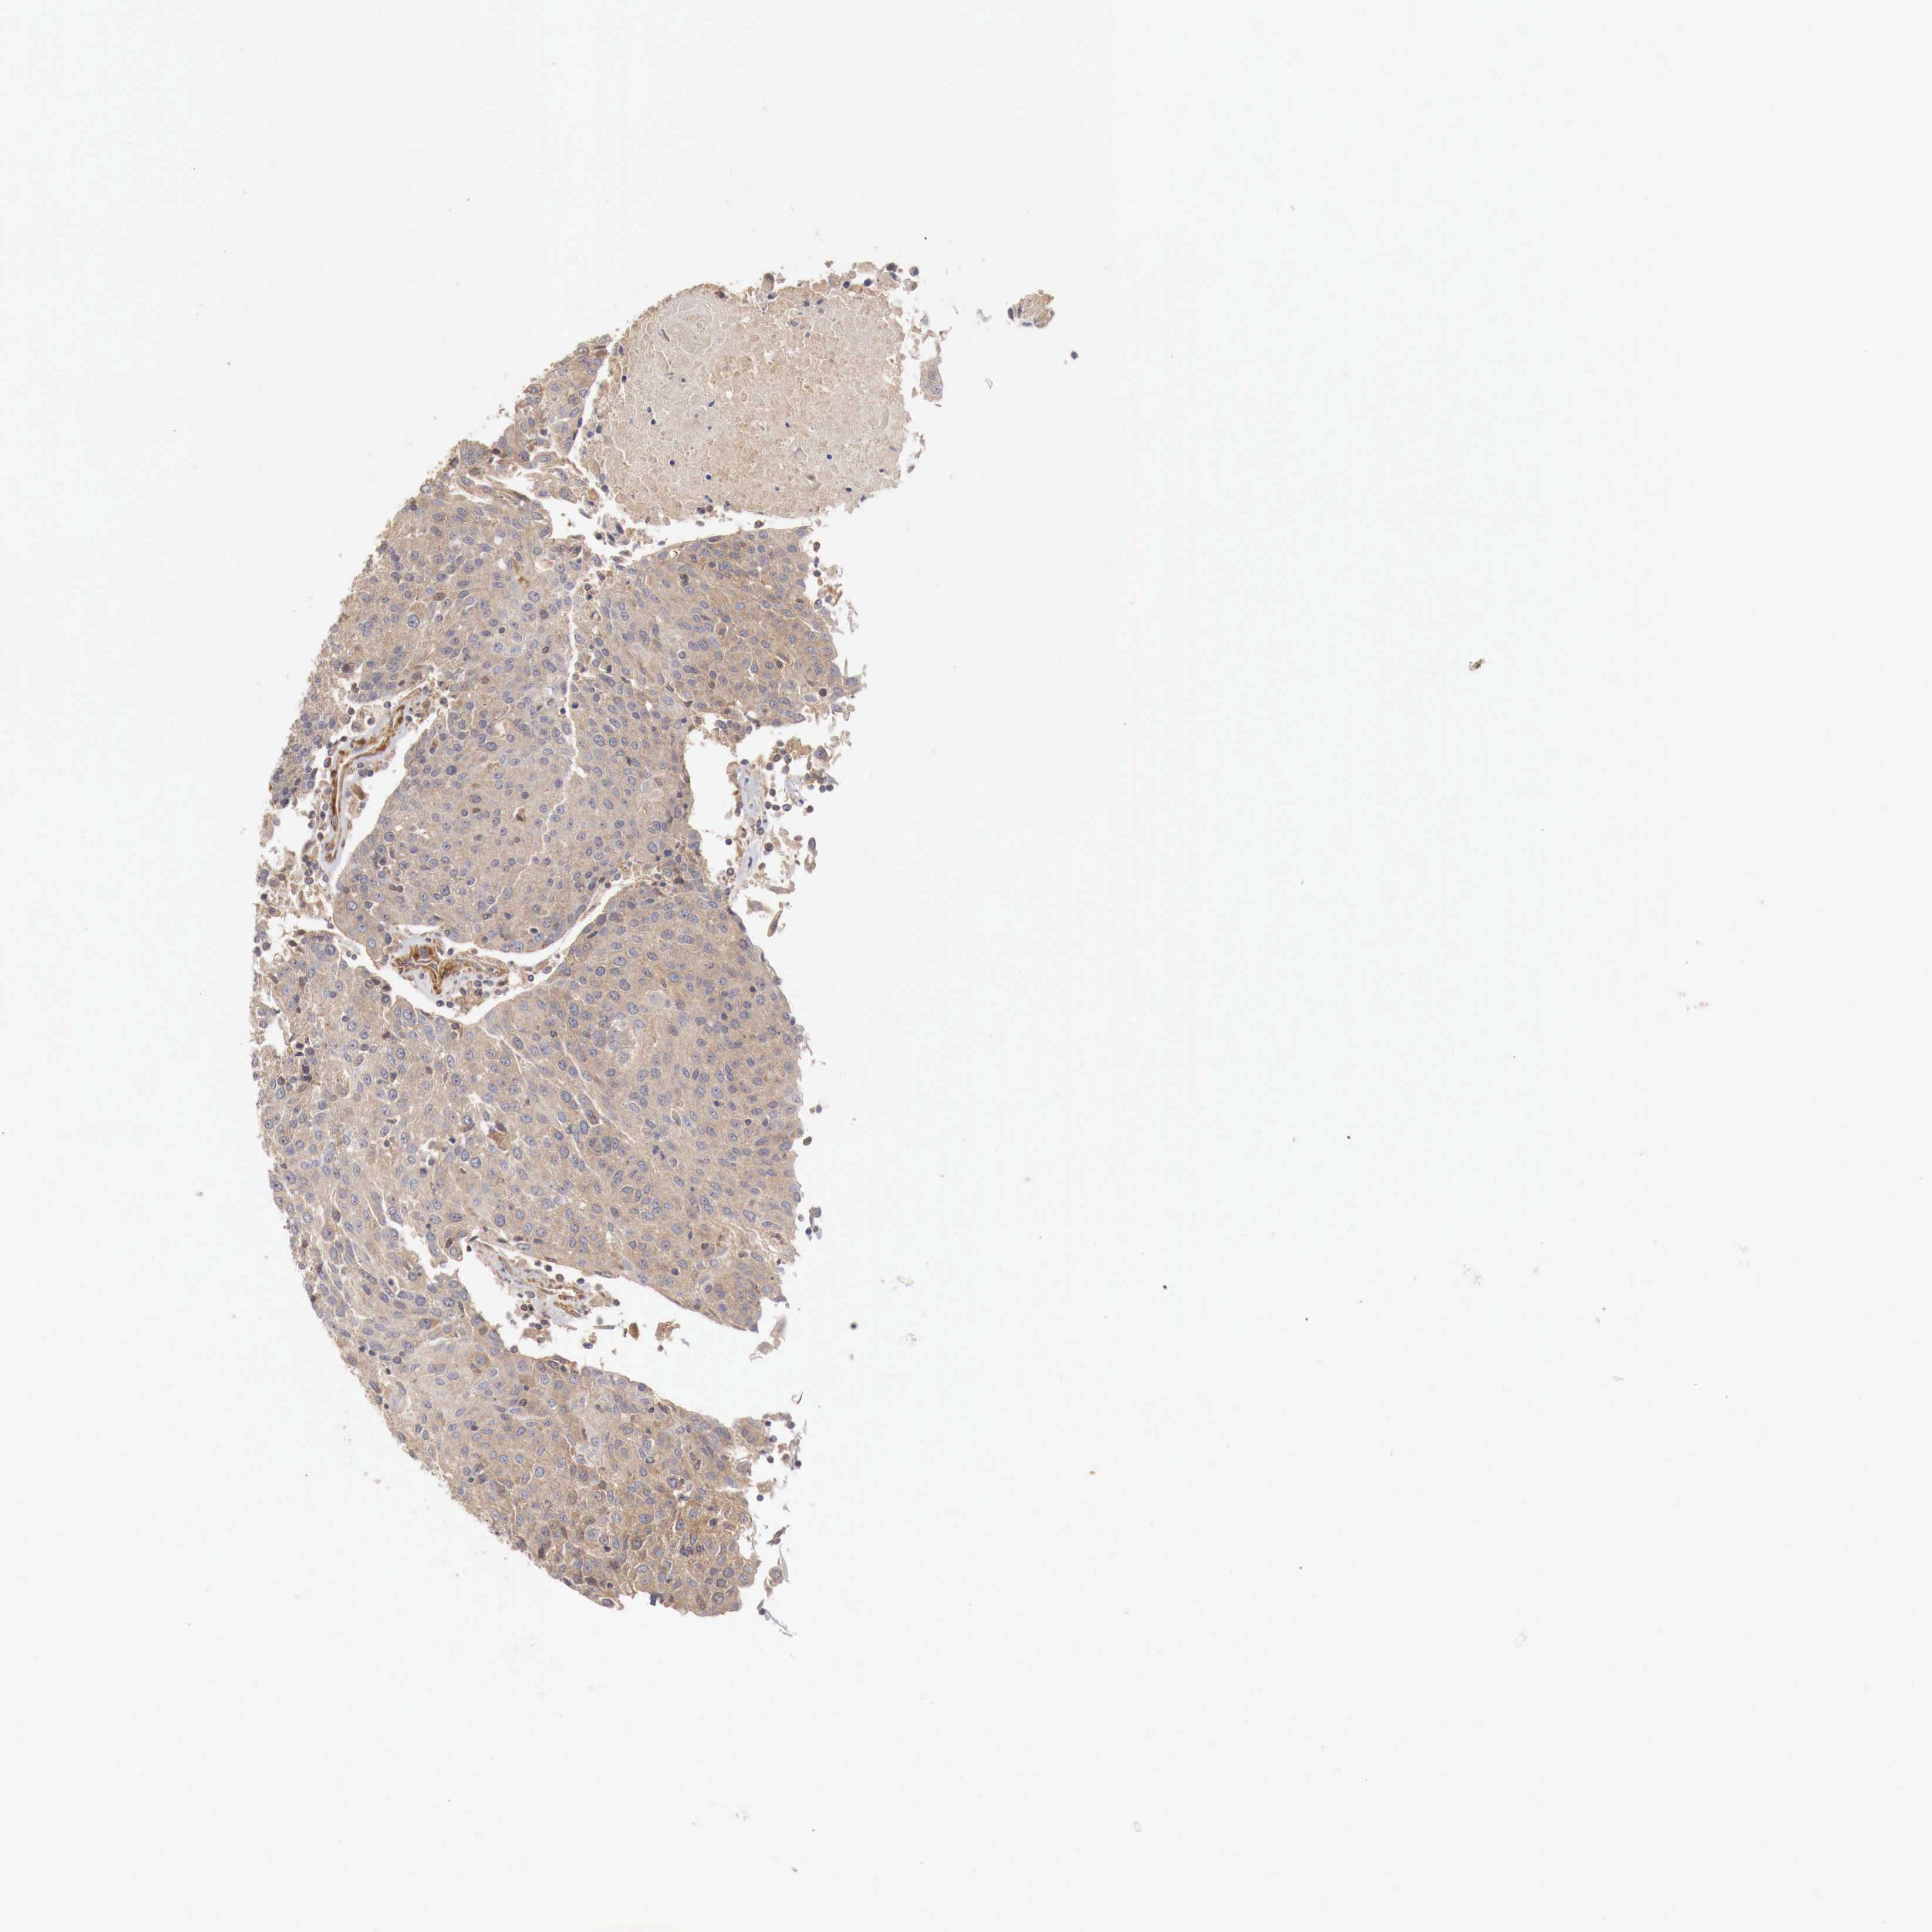

UROTHELIAL CANCER - Protein expressioni

A mouse-over function shows sample information and annotation data. Click on an image to view it in a full screen mode. Samples can be filtered based on level of antibody staining by selecting one or several of the following categories: high, medium, low and not detected. The assay and annotation is described here.

Antibody stainingi

Antibody staining in the annotated cell types in the current human tissue is reported as not detected, low, medium, or high, based on conventional immunohistochemistry profiling in selected tissues. This score is based on the combination of the staining intensity and fraction of stained cells.

Each image is clickable and will lead to virtual microscopy that enables deeper exploration of all samples and also displays staining intensity scores, fraction scores and subcellular localization as well as patient and tissue information for each sample.

Antibody HPA000429

Staining

High

Medium

Low

Not detected

Intensity

Strong

Moderate

Weak

Negative

Quantity

>75%

75%-25%

<25%

None

Location

Nuclear

Cytoplasmic/membranous

Cytoplasmic/membranous,nuclear

Urothelial carcinoma, High grade